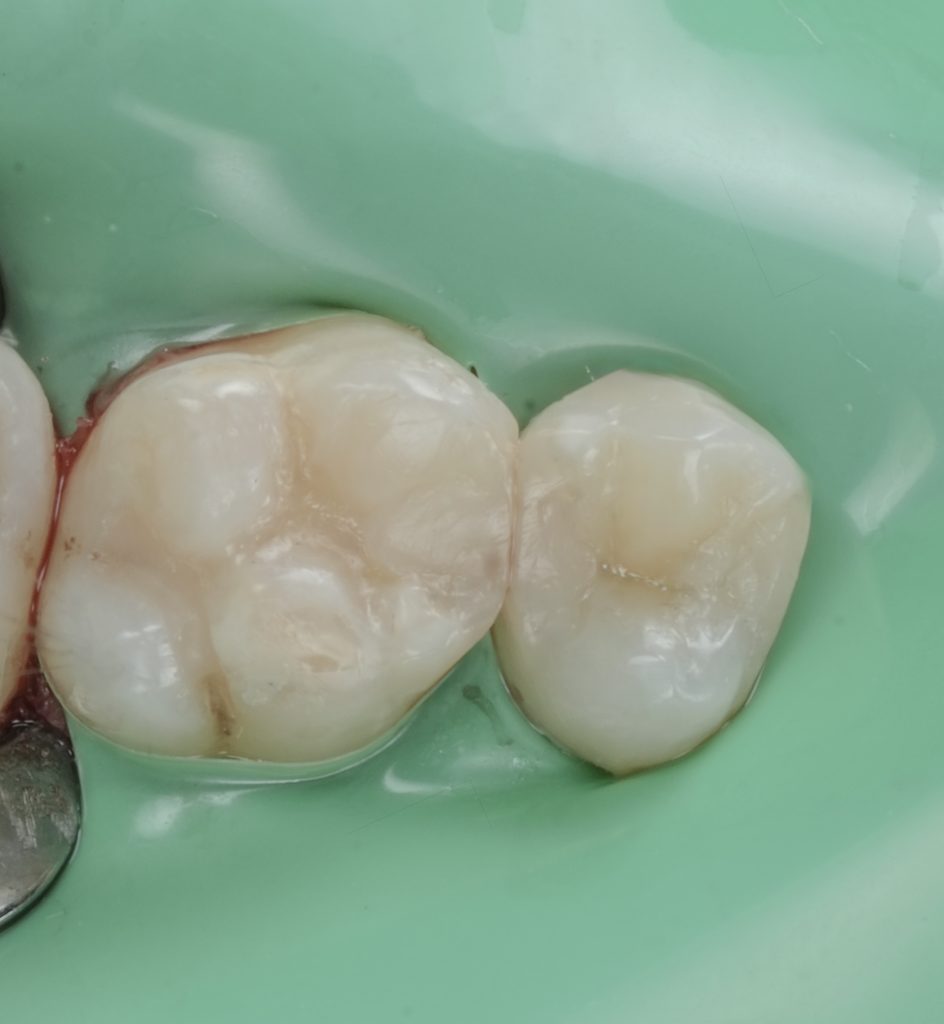

Images to place

- Fig. 12: Immediate post-op occlusal (dam still on).

- Fig. 13: Post-op occlusal after polish (dam off).